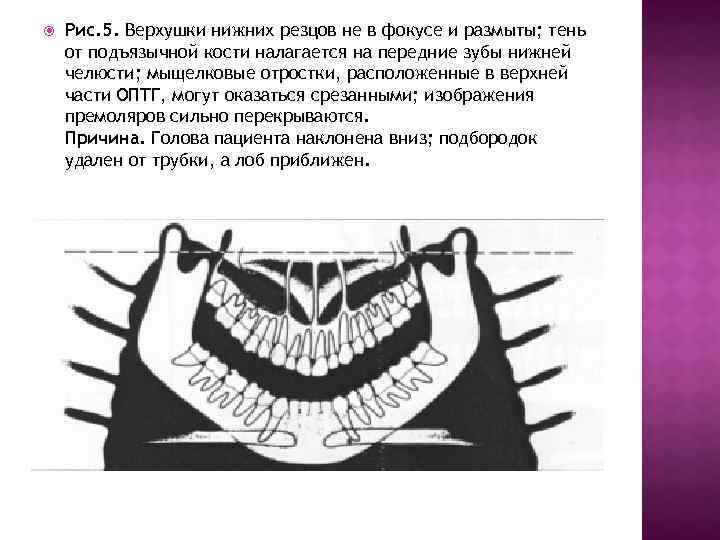

Рис. 5. Верхушки нижних резцов не в фокусе и размыты; тень от подъязычной кости налагается на передние зубы нижней челюсти; мыщелковые отростки, расположенные в верхней части ОПТГ, могут оказаться срезанными; изображения премоляров сильно перекрываются. Причина. Голова пациента наклонена вниз; подбородок удален от трубки, а лоб приближен.